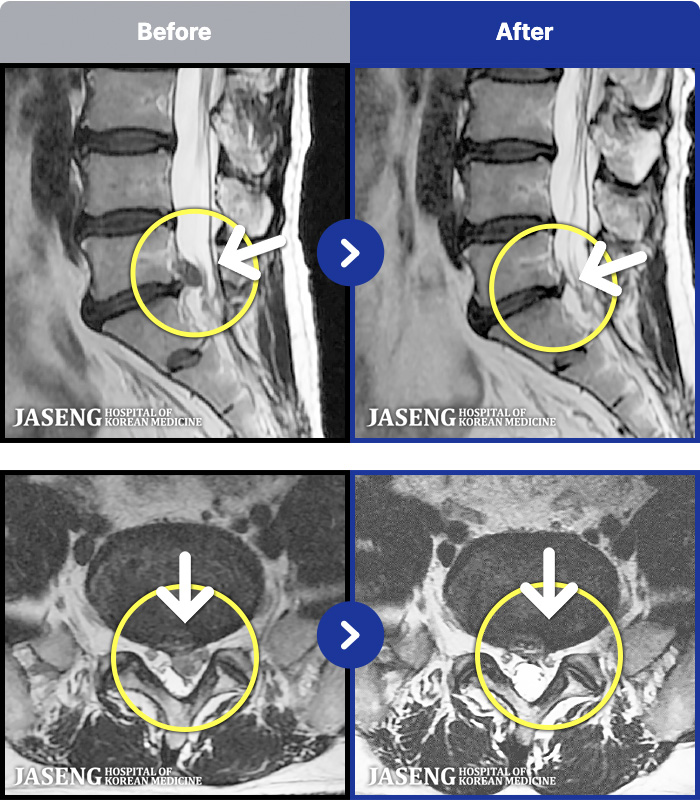

1,287 MRI ũ ʸ Ȯϼ.